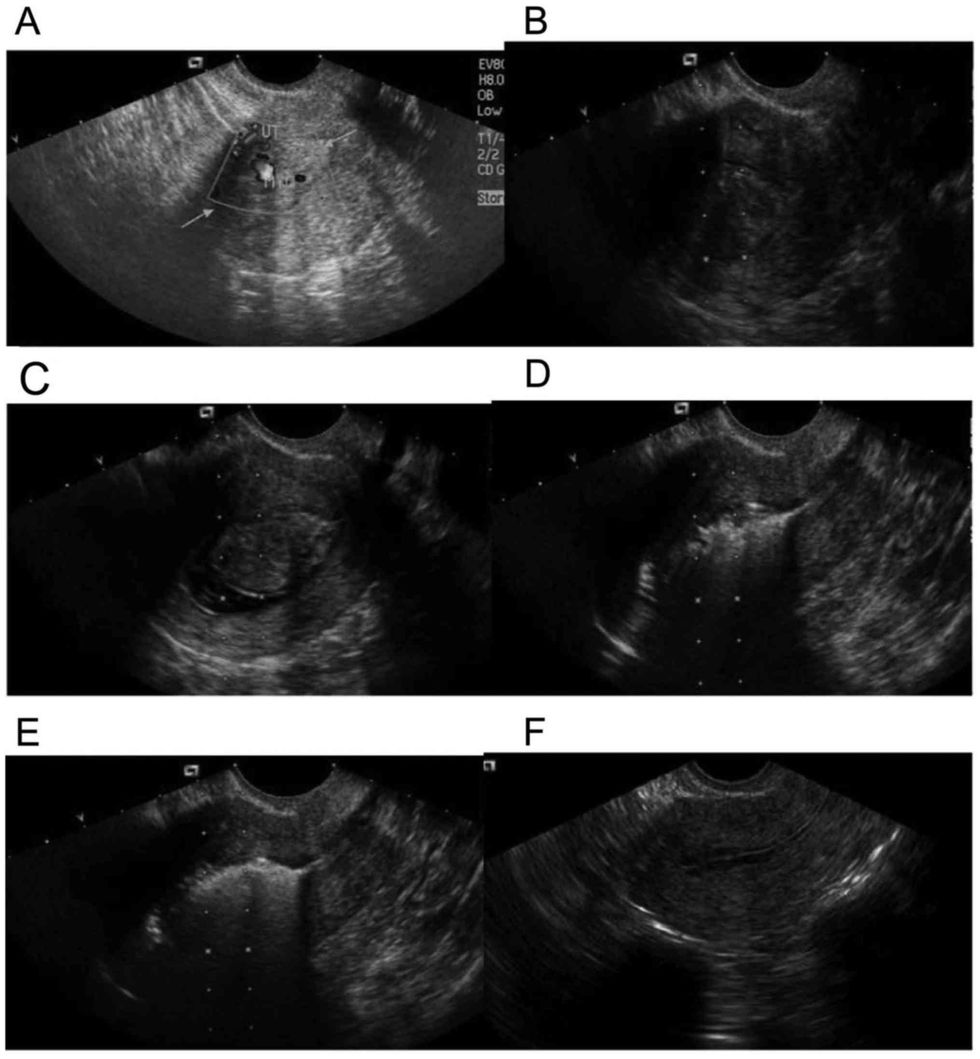

Si te çdo sëmundje tjetër, edhe këtu është me rëndësi anamneza (ankesat e pacientes). Pastaj bëhet ekzminimi gjinekologjik dhe sonografia (ultrazëri) vaginal. Gjatë ekzaminimit gjinekologjik, mund te konstatohet rritje ose edhe deformim i mitrës.

Në ultrazë zakonisht shihen mirë miomet ku mund të përcaktohet lokalizimi, madhësia dhe numri i tyre. Këto të dhëna janë të rëndësishme për formën e terapisë e cila pason.